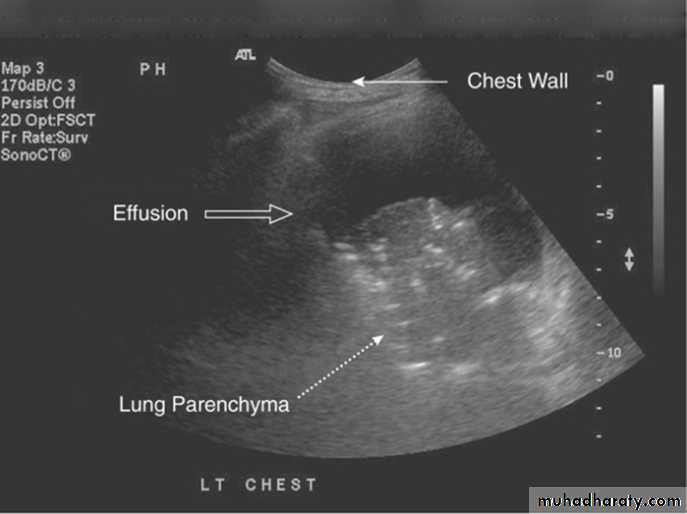

Radiology

Chest X-RayUltrasound (US) is able to demonstrate small effusions.

Small pleural effusions can be detected best by ultrasound (or CT).The most important laboratory parameter of pleural fluid is total protein, distinguishing trans- and exudates.